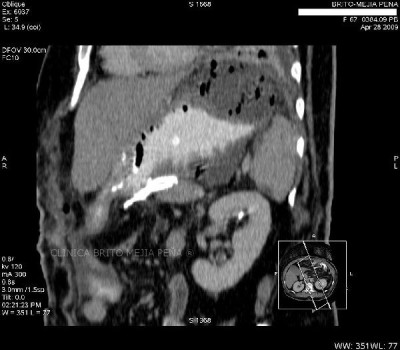

Colangiocarcinoma axial